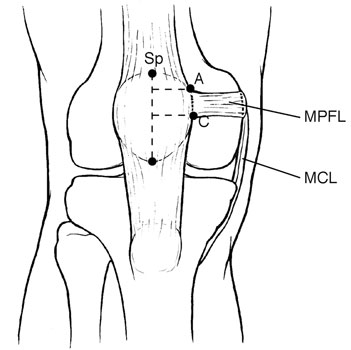

MPFL The Little Ligament That Could ProActive Physical Therapy online, Medial Patello Femoral Ligament MPFL Reconstruction online, Patellofemoral Ligament Reconstruction Knee Surgeon South online, Arthroscopic reconstruction of the medial patellofemoral ligament online, Medial Patellofemoral Ligament Tears Minneapolis MN Sports online, Medial Patellofemoral Ligament Reconstruction Techniques online, Patellofemoral Instability in the Skeletally Immature Patient A online, Medial Patellofemoral Ligament Surgery In Tamilnadu online, Physical Therapy for Medial Patellofemoral Ligament Injury online, PDF Management of medial patellofemoral ligament injury A case online, Medial Patellofemoral Ligament Injury MPFL Specialist Sugar online, Arthroscopy Journal on X online, The Medial Patellofemoral Ligament of the Knee by Nabil Ebraheim online, Figure 4 from The medial patellofemoral ligament Review of the online, Medial patellofemoral ligament reconstruction technique online, Graphic illustration of double bundle medial patellofemoral online, MPFL reconstruction animation online, What is the difference between MCL and MPFL ligaments and does online, Dynamic Anatomical Reconstruction of Medial Patellofemoral online, MPFL Injury Medial Patellofemoral Ligament MPFL Tear online, Your Patellofemoral Ligaments and Cartilage Spring Loaded Technology online, MPFL Reconstruction Hertfordshire Patellar Instability online, Medial Patellofemoral Ligament Reconstruction Complete Orthopedics online, Medium to long term outcomes of medial patellofemoral ligament online, Figure Diagram of the patellofemoral ligaments. Contributed by online, Medial Patellofemoral Ligament Tear Moreno Valley CA MPFL online, Medial Patellofemoral Ligament Of The Knee Anatomy Everything You Need To Know Dr. Nabil Ebraheim online, The Medial Patellofemoral Ligament MPFL The Basics BSM Foundation online, Medial Patellofemoral Ligament MPFL Reconstruction Knee online, Medial Patellofemoral Ligament MPFL Gorav Datta online, Medial Patellofemoral Ligament Reconstruction Sydney Knee online, Medial Patellofemoral Ligament Injury Recovery Capital Area PT online, Medial Patellofemoral Ligament MPFL Reconstruction HSS online, Medial Patellofemoral Ligament Injury MPFL Tear MPFL online, Medial Patellofemoral Ligament MPFL Physiopedia online, Product Info: Medial patellofemoral ligament online.